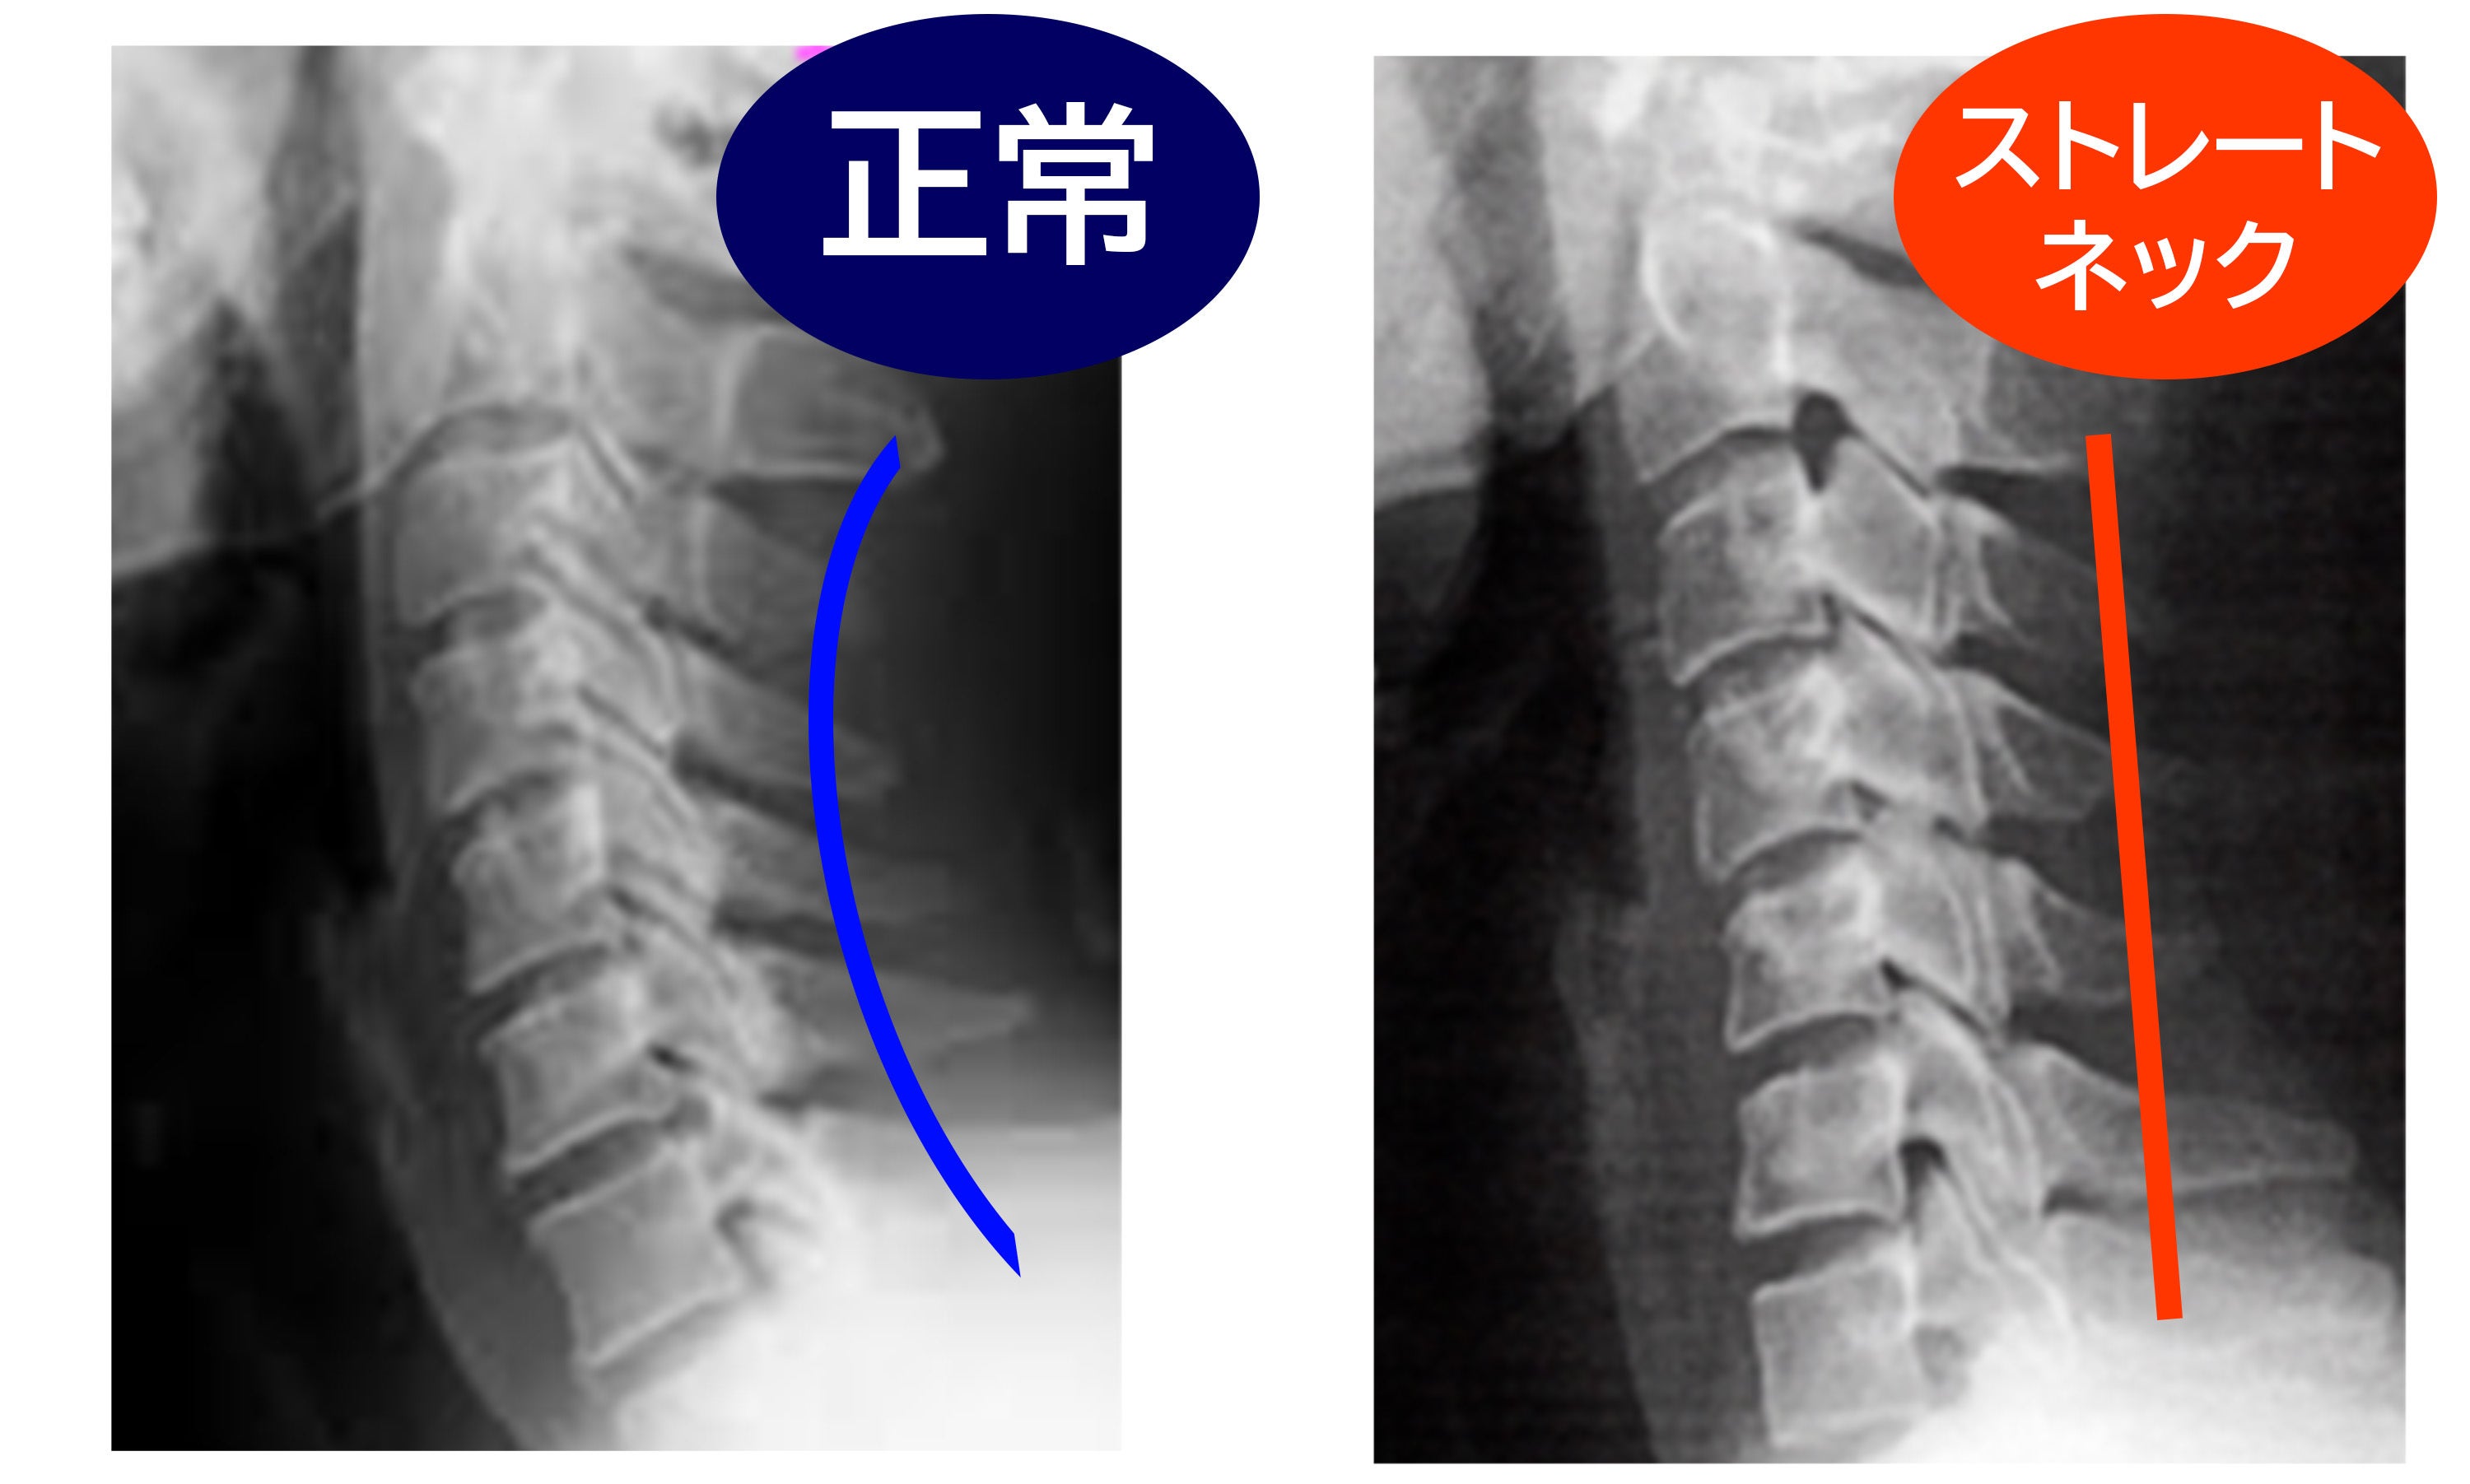

健康な頸椎曲線をどんな体制でも保つことができたら。

現代に蔓延するストレートネックを何とかしたい。

誰でも簡単に健康な頸椎曲線を目指せる快眠枕の開発を進めました。